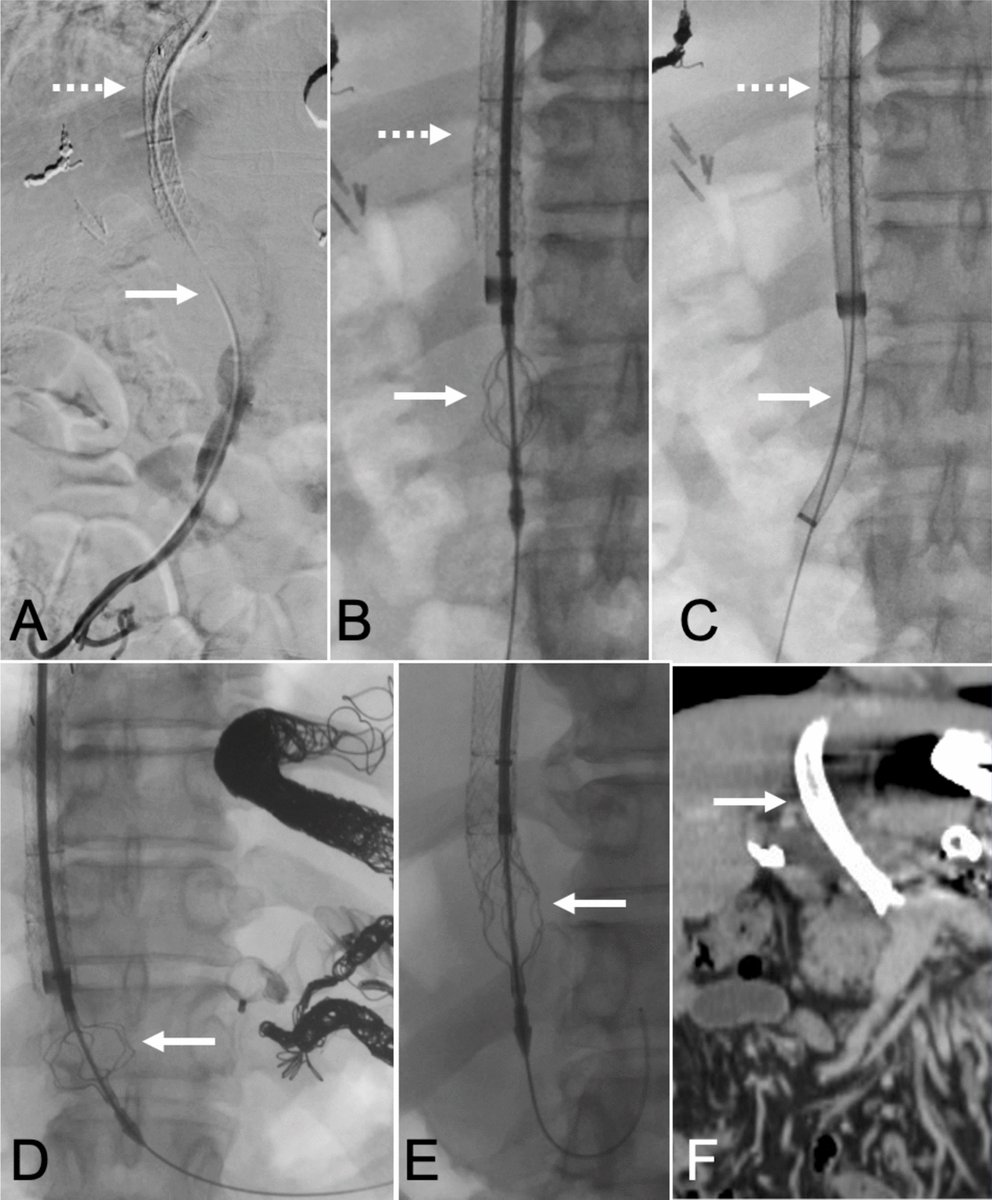

MARGIN: Randomized Trial of Arterial CT Portography Versus Standard Imaging Guidance for Percutaneous Thermal Ablation of Colorectal Liver Metastases